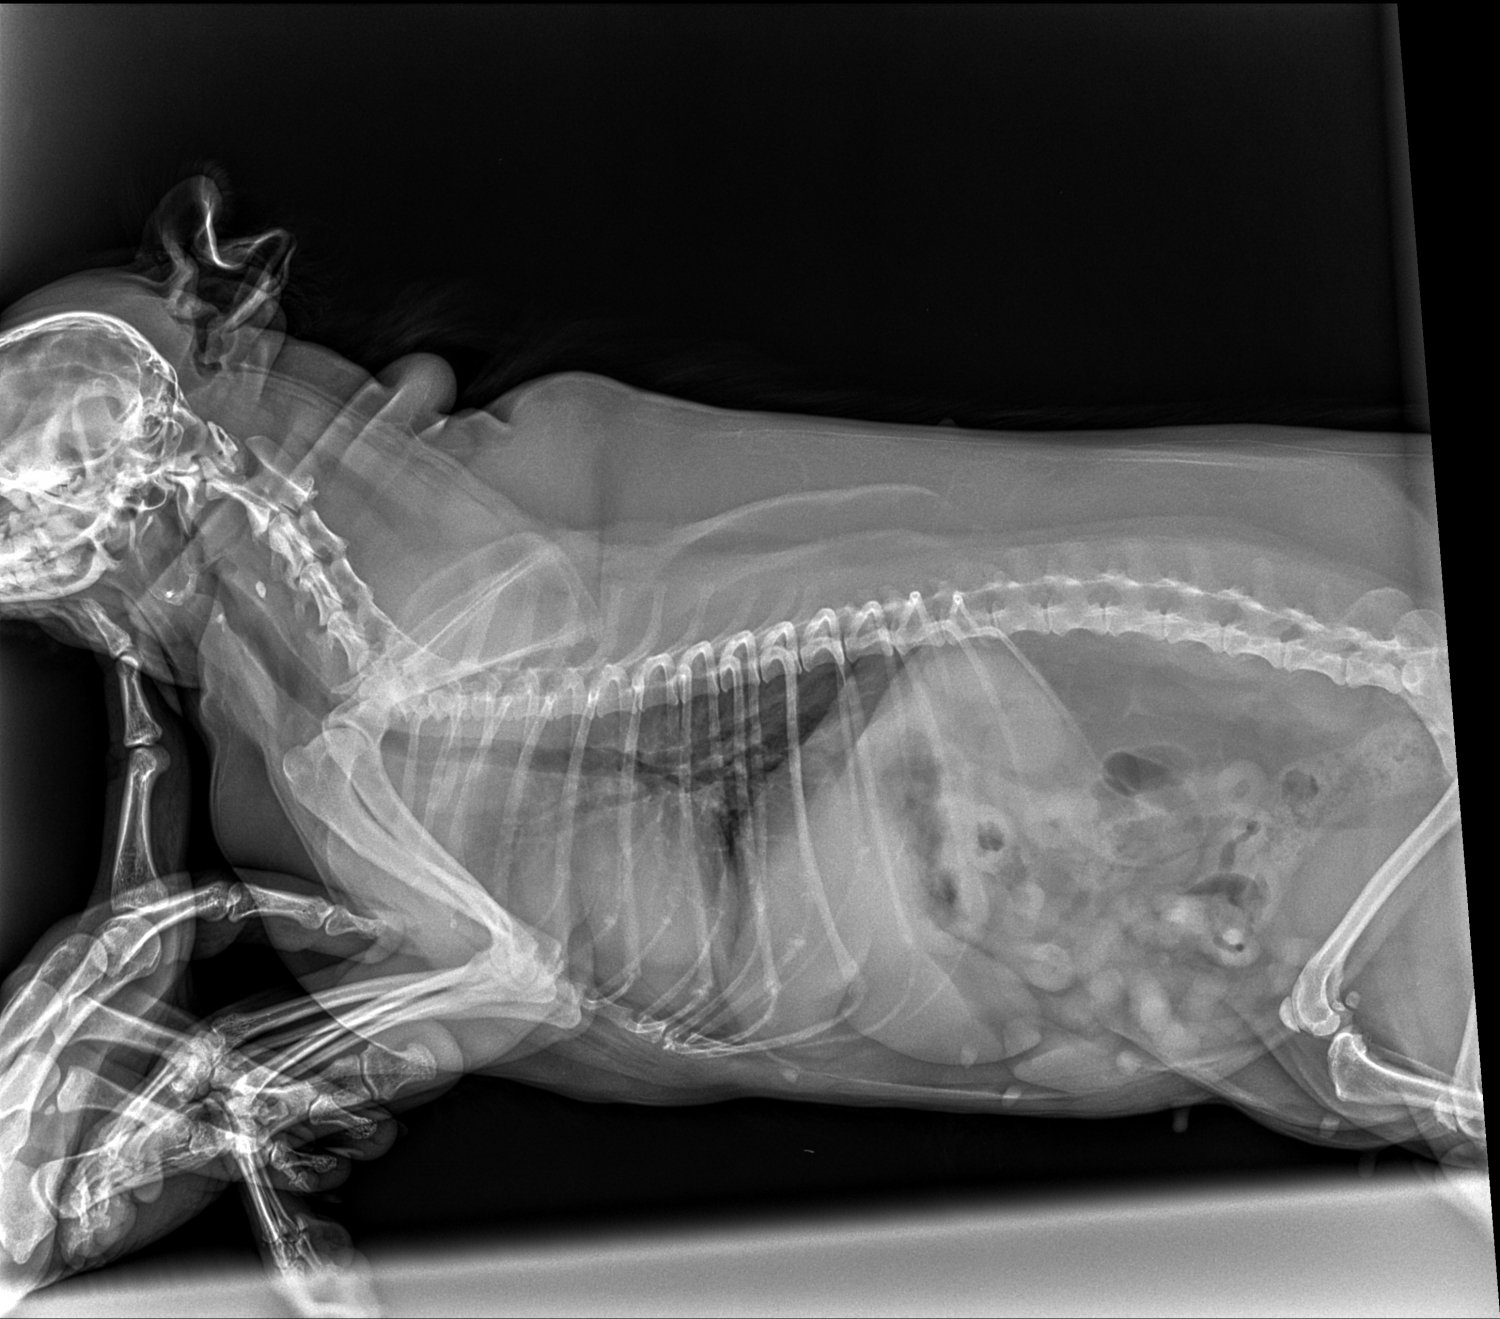

Zawsze to ja pomagam innym, ale tym razem zmuszona jestem o tą pomoc prosić. Moja ukochana psia córeczka od pewnego czasu ma ataki, które objawiają się zesztywnieniem całego ciała lub ograniczoną ruchowością i dużą trudnością w poruszaniu się. Weterynarz podejrzewał najpierw, że jest to na tle neurologicznym, została przebadana, lecz nie stwierdzono żadnych nieprawidłowości. Podejrzewał, że jest to na tle nerwowym, więc brała leki uspokajające, odstesowujace. W między czasie powtórnie wielokrotnie badana, ze względu na dalsze ataki. Badania wychodziły dobrze. W niedzielę 22 sierpnia od ok. godz. 14:00 do 22:00 (do póki nie zasnela) miała problem z poruszaniem się, każdy krok sprawiał jej trudność. W poniedziałek znów udałam się do weterynarza i pojawiły się podejrzenia, że jest to jednak na tle ortopedycznym. Dziś trafiłam do świetnego ortopedy, który wykonał szereg badań, w tym RTG - zdjęcia i opis załączone. Okazuje się, że jest duży problem zwyrodnienia. Otrzymała leki i konieczne jest wykonanie MRI oraz prawdopodobnie operacja. Nieststy to wszystko wykracza poza moje możliwości finansowe, dlatego bardzo chciała bym prosić Państwa o wsparcie. Ona jest dla mnie jak córka, bez niej nie wyobrażam sobie życia i zrobię wszystko, aby była zdrowa. Będę ogromnie wdzięczna za każdą złotówkę przekazaną na jej leczenie. Osobą zainteresowanym mogę przesłać filmiki, na których widać jak duży jest to problem i jak bardzo potrzebna jest jej pomoc.